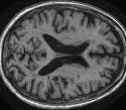

| MRI | PET | U-PET | U-PET (no att.) | pix2pix |

4.0.2 Qualitative Results

Looking at sample synthetic PET images in Fig. 3, it can be seen that all of the models are able to make reasonable predictions. The outputs of the U-PET and U-PET (no att.) look very similar and are smoothed compared to the input. The pix2pix predicts more details, which seem to be important for the discriminator. However, even though this model has finer predictions, the intensity values are worse compared to the U-PET and U-PET (no att.) as seen in Fig. 2; an example is given in Fig. 3 in the second row.

From a clinical perspective, the synthetic generated PET show a smoother version of the real PET images but keep the same pattern of FDG uptake, especially, hypometabolism in the respective brain areas. This backs up our hypothesis, that MRI contains information that correlates with the functional information of PET images. Moreover, the synthetic PET could be used as complementary visualization for physicians beyond the task of classification.